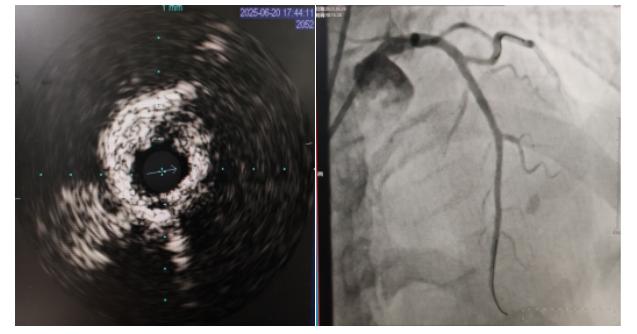

術(shù)中,趙慶禧主任醫(yī)師、雷剛副主任醫(yī)師運(yùn)用IVUS血管內(nèi)超聲技術(shù)評(píng)估,發(fā)現(xiàn)患者前降支、對(duì)角支0.1.1型真性分叉病變,前降支近中段嚴(yán)重鈣化、成角并99%狹窄,對(duì)角支近段嚴(yán)重鈣化并99%狹窄,傳統(tǒng)冠狀動(dòng)脈旋磨術(shù)容易引起冠狀動(dòng)脈穿孔,決定采用沖擊波球囊技術(shù)即血管內(nèi)沖擊波鈣化碎裂術(shù)對(duì)患者嚴(yán)重鈣化的血管進(jìn)行介入治療。通過球囊低壓擴(kuò)張,向血管病變處發(fā)射非聚焦、低能量、脈沖式的沖擊波,對(duì)前降支及對(duì)角支進(jìn)行了連續(xù)5個(gè)周期沖擊波脈沖治療,安全地碎裂淺、深層鈣化,原本看似堅(jiān)不可摧的環(huán)形鈣化區(qū)逐漸顯現(xiàn)出了裂痕,多處關(guān)鍵位置發(fā)生了斷裂,充分預(yù)處理后于前降支近中段串聯(lián)植入支架3枚,對(duì)角支植入藥物球囊,術(shù)后造影見血管病變處狹窄完全消失,支架膨脹完全,貼壁良好,各項(xiàng)生命體征平穩(wěn),手術(shù)非常成功,患者返回心血管內(nèi)科病房繼續(xù)治療,并于4天后順利出院。